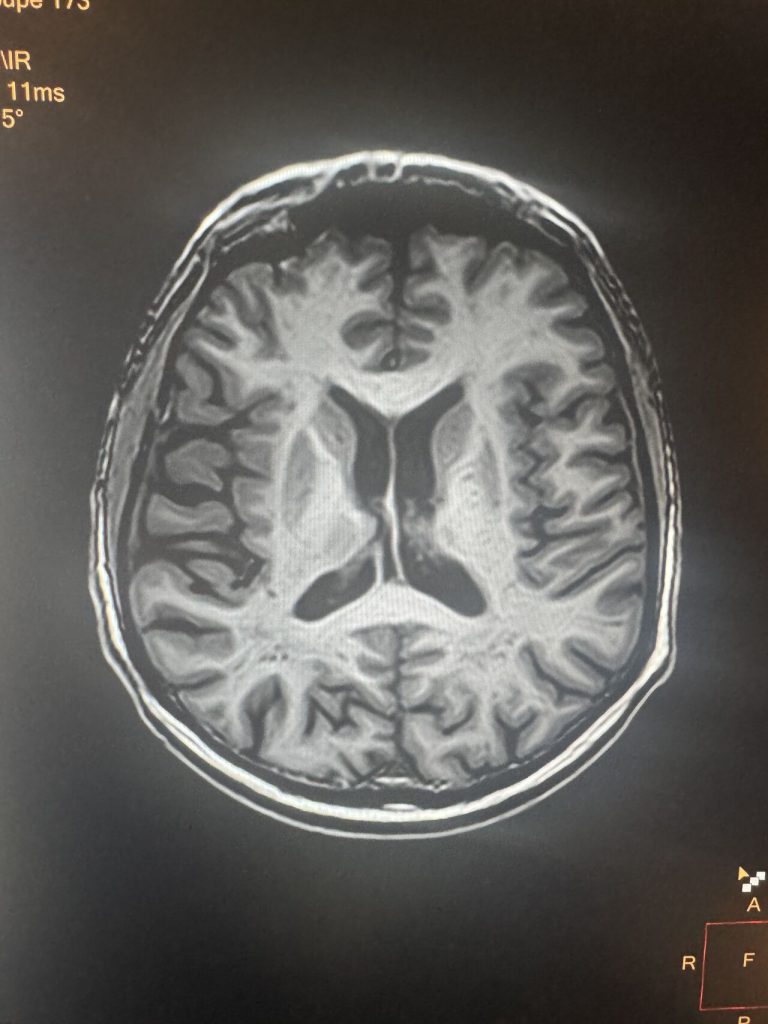

L’acquisition de notre première IRM 3T va être un véritable tournant pour la performance diagnostique notamment dans notre pratique Neuroradiologique:

👉imagerie de l’épilepsie

👉imagerie neurovasculaire: depistage de malformation vasculaire, exploration distale des vaisseaux intracrâniens

👉Imagerie de paroi intracrânienne et imagerie de plaque HR des carotides

👉imagerie hypophysaire

👉imagerie orbitaire

👉imagerie orl à la recherche d’hydrops

👉possibilité de développer l’IRM fonctionnelle cérébrale